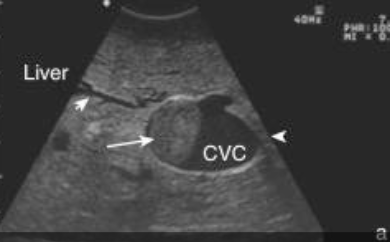

how is vena cava thrombosis diagnosed?

1. endoscopy (visualization of blood in trachea)

2. ultrasound: liver abscess, dilation of CVC